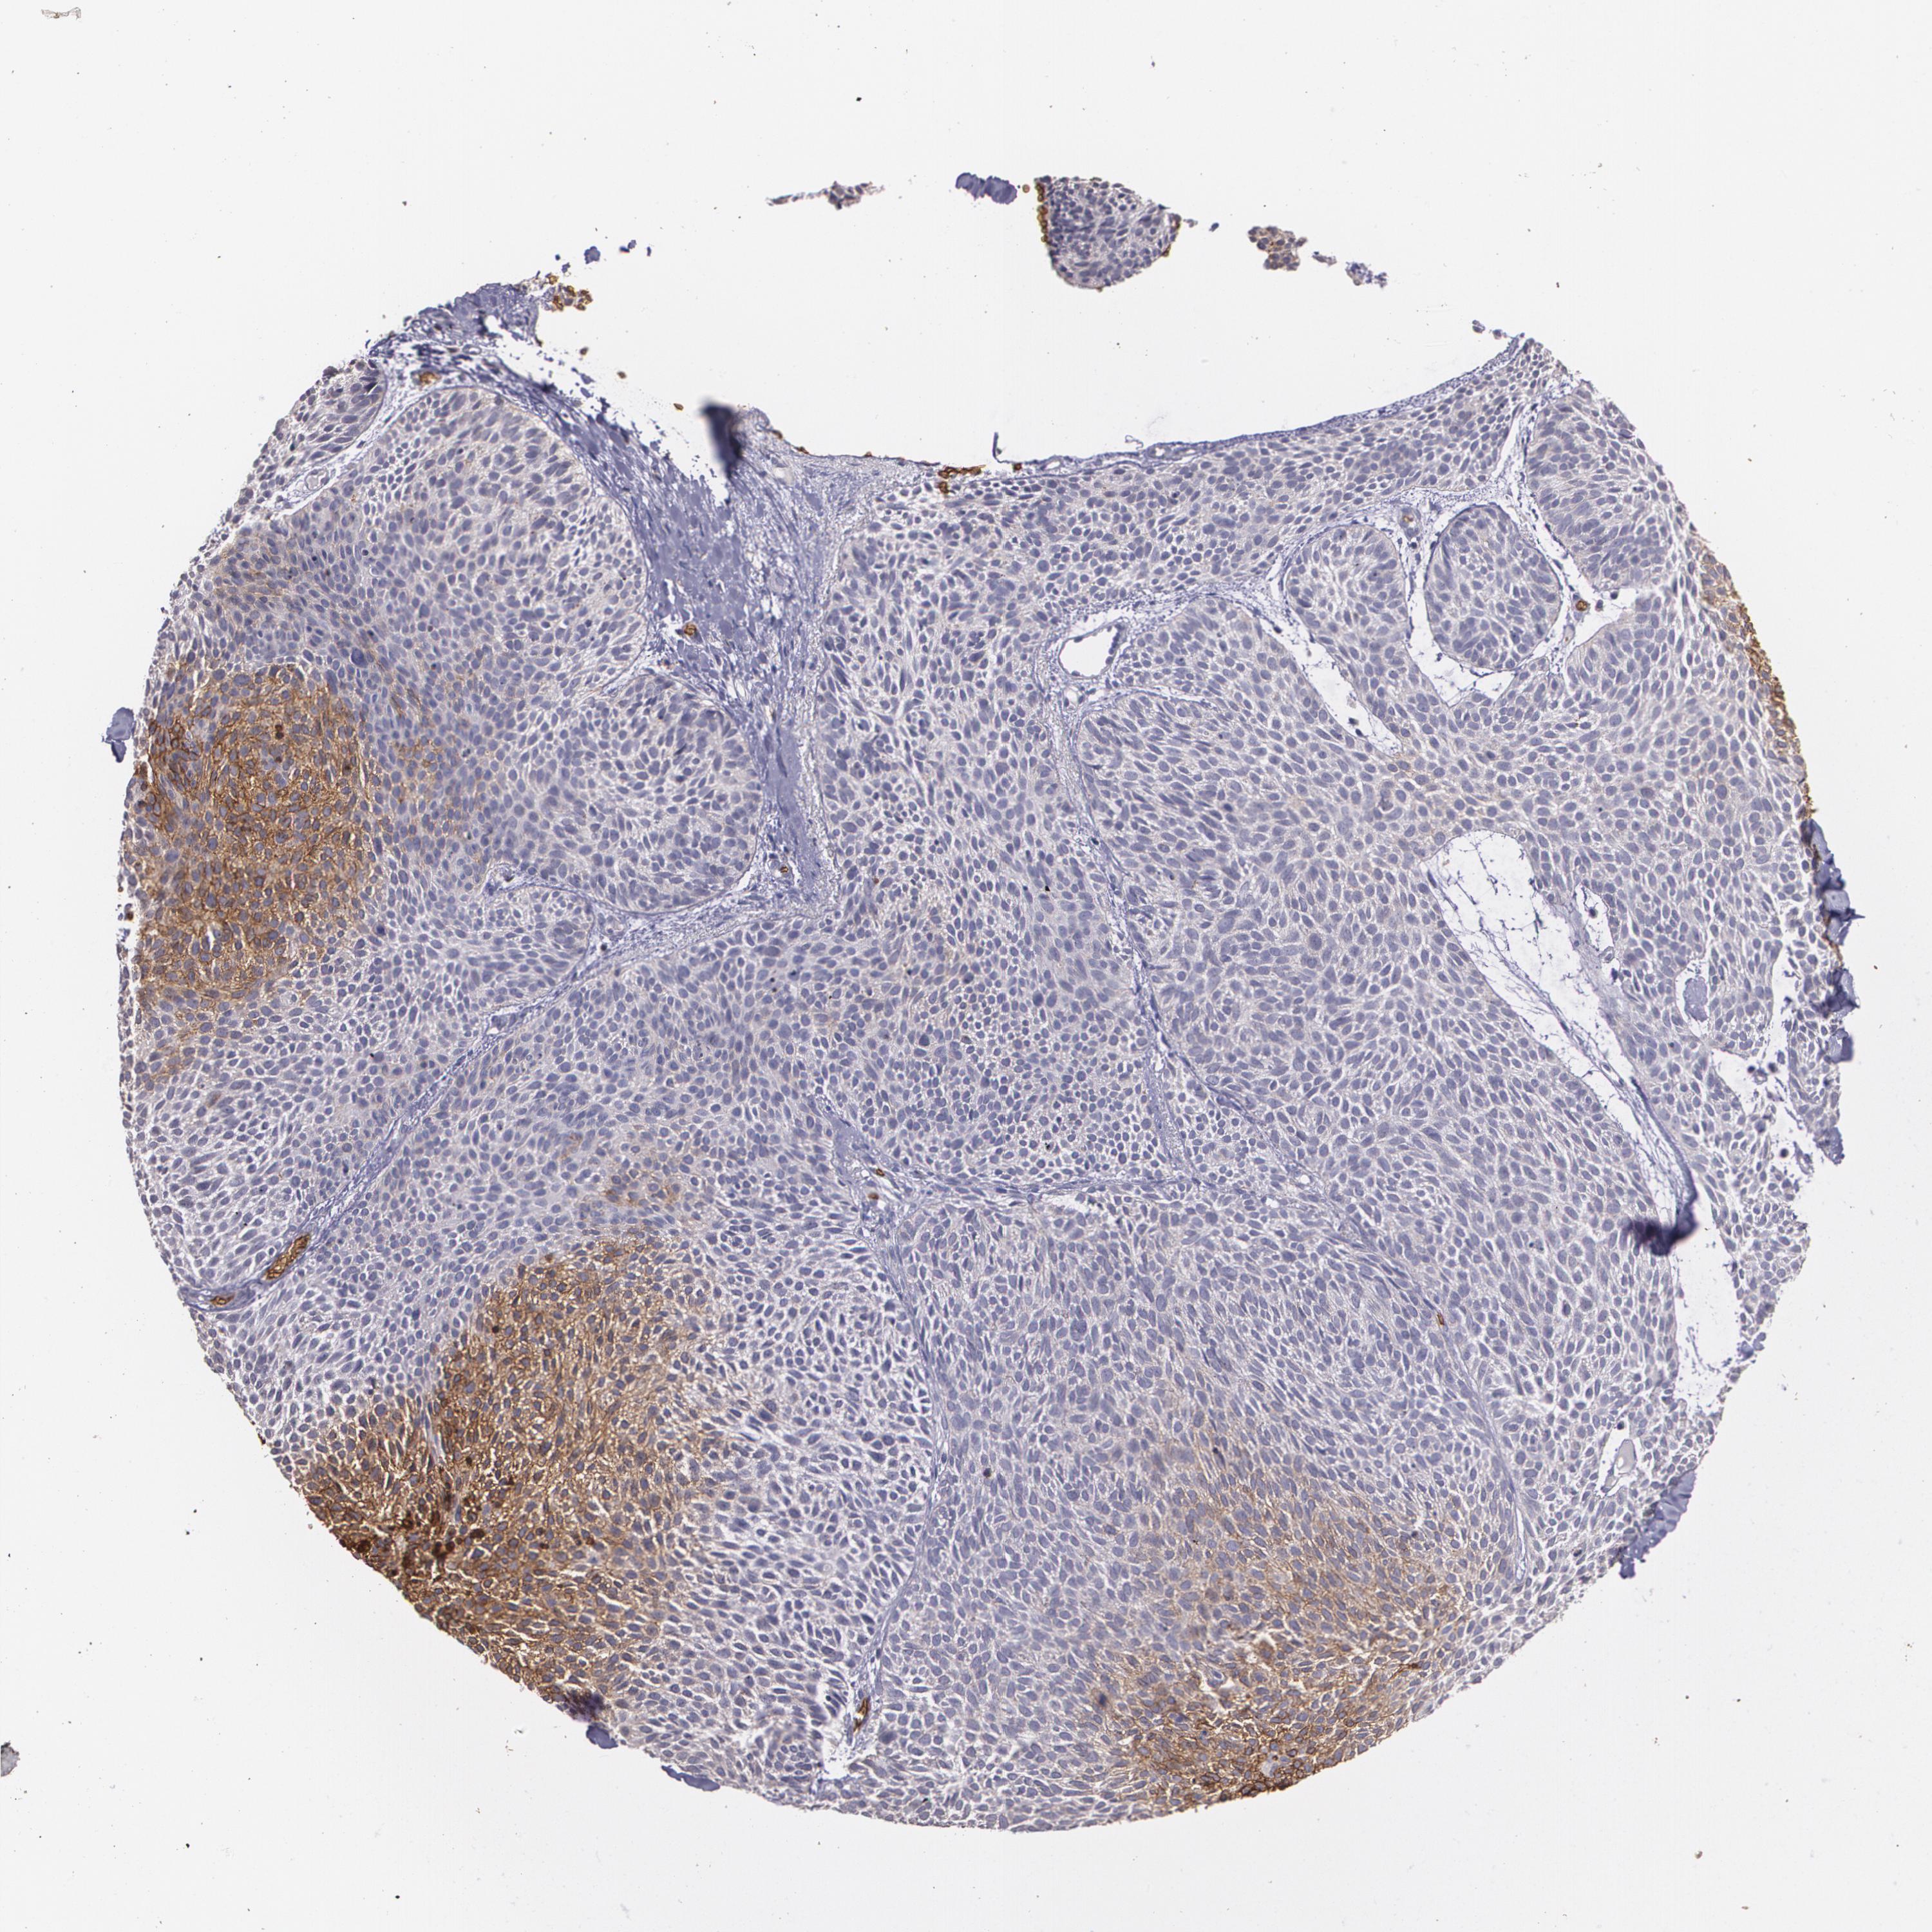

SKIN CANCER - Protein expressioni

A mouse-over function shows sample information and annotation data. Click on an image to view it in a full screen mode. Samples can be filtered based on level of antibody staining by selecting one or several of the following categories: high, medium, low and not detected. The assay and annotation is described here.

Each image is clickable and will lead to virtual microscopy that enables deeper exploration of all samples and also displays staining intensity scores, fraction scores and subcellular localization as well as patient and tissue information for each sample.

Antibody HPA031345

Antibody HPA058494

Antibody CAB002759

Squamous cell carcinoma, NOS